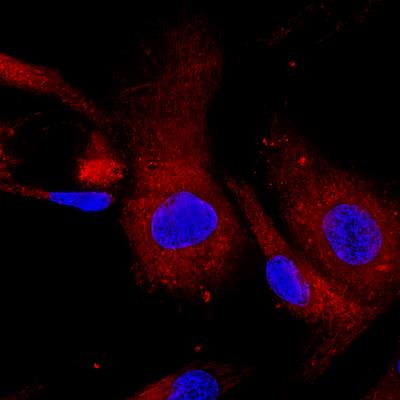

Immunomodulation of MSCs in Tissue Repairing and Regeneration

- Yanwen Peng

- Qunzhou Zhang

- Weiqiang Li

- 44,148 views

- 9 articles